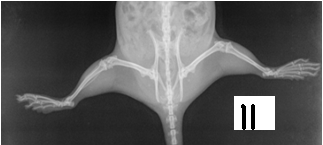

Photographs. 1, 2, 3 are of Anti-arthritic activity of Effect of Petroleum ether and Methanol extract of leaf of Pergularia daemia [Forsk]

Radiographic Analysis

On the 21st day immediately after measurement of paw volume displacement and recording of secondary lesions, the one rat from each group was animals were sacrificed by cervical dislocation and carotid bleeding and subjected to the radiological examination using Agfa digital System and Seimens X ray machine. These radiographs were evaluated for any deformity especially for soft tissue swelling and bone erosion, joint space narrowing by independent qualified person. [21]

Radiographic analysis is considered to be the best tool to screen the any drug in this regard. In present study radiographic analysis of the joint showed significant prevention in progress of joint [20, 21]. By synthetic therapy, there is rapid reduction in inflammation in arthritis is observed with corticosteroids but the effect of these drugs were for short time. Corticosteroids become less effective over time where as arthritis is usually active for years together [22]. From the above research work, the leaf extract of Pergularia daemia [Forsk] is a good substitute for corticosteroids therapy for arthritis.